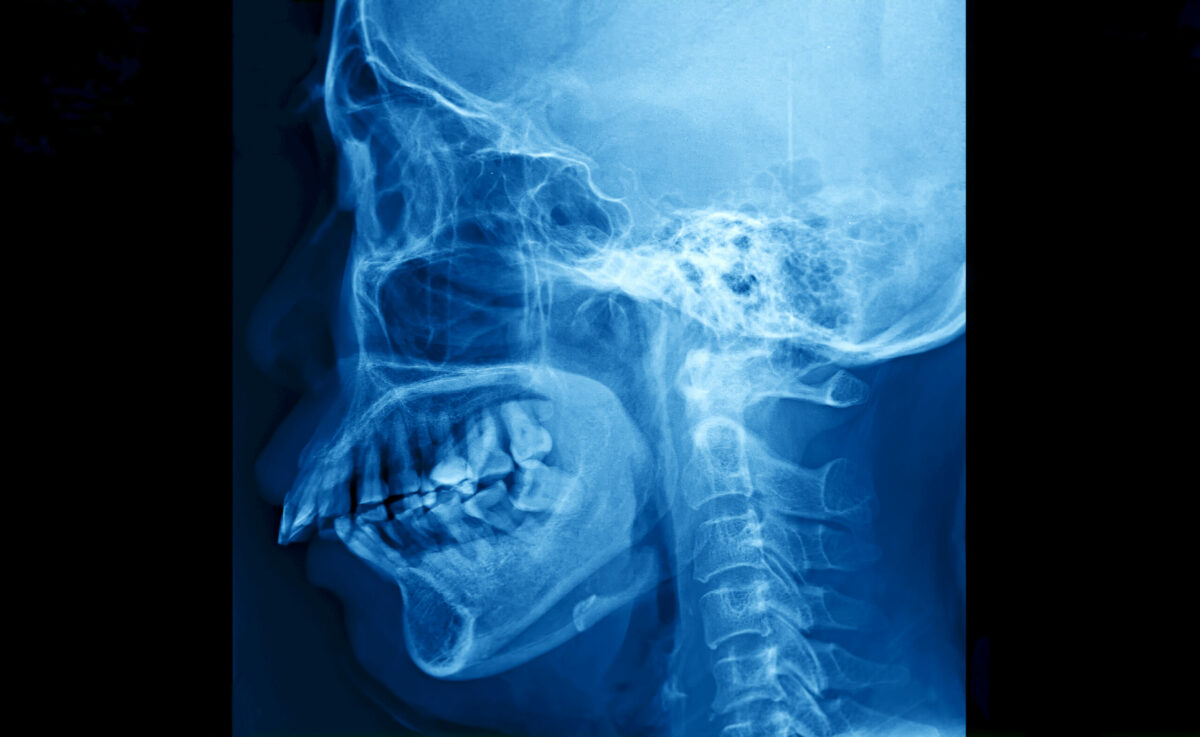

- Chest or neck X-ray – This imaging test often is not needed to diagnose the condition but doctors perform it to make sure you have epiglottitis. If this test shows a thumbprint in the neck, usually it indicates an enlarged epiglottis.